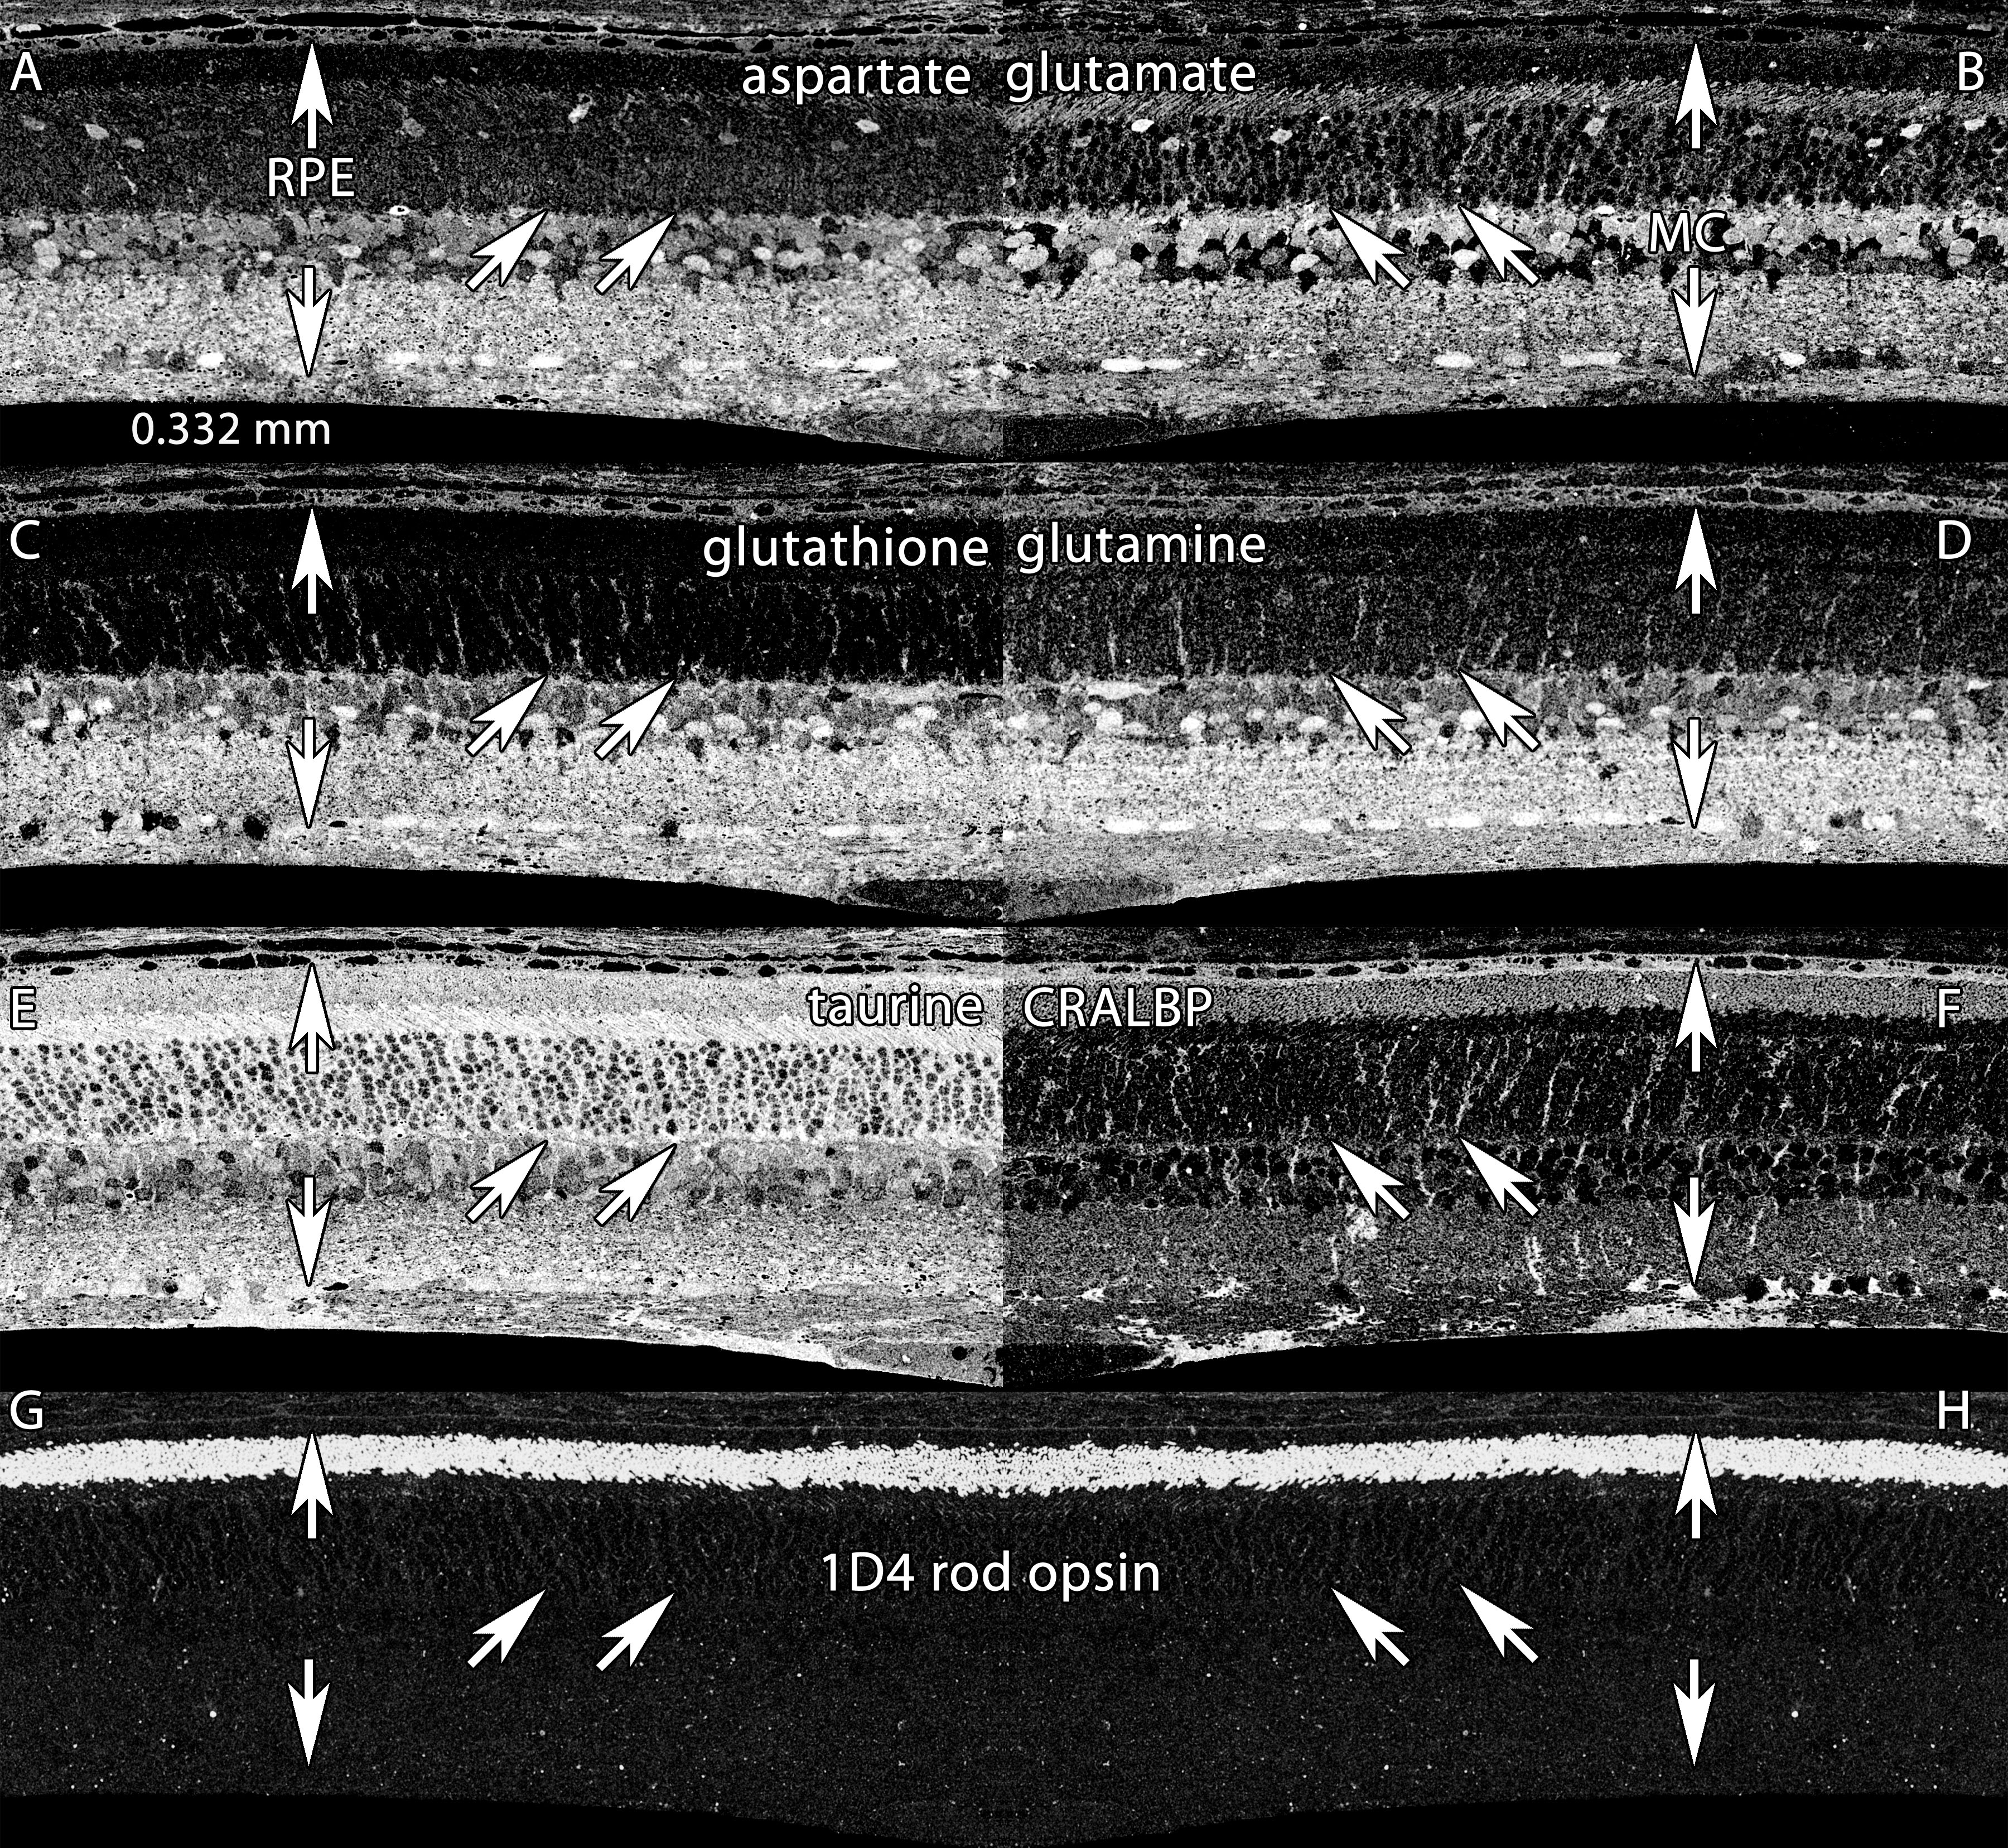

Figure 2. Basic molecular signatures in the normal albino rat retina. Visualization: Quantitative gray-scale images displayed as intensity

in mirror-image pairs (AB, CD, EF, GH). Up arrows, retinal pigment epithelium (RPE); down arrows, Müller cell (MC) end feet;

oblique arrows mark the border of the outer nuclear and outer plexiform layers. Panels are 0.332 mm wide. A: Aspartate is high in the RPE, in cone photoreceptors and various neurons of the neural retina but low in rods. B: Glutamate levels are high in neurons and lower in MC. C: Glutathione levels are high in the RPE and MCs, but very low in photoreceptors. D: Glutamine is high in all cells, but especially MCs. E: Taurine is high in the RPE, photoreceptors and MCs, and somewhat lower in neurons. F: cytosolic retinal binding protein (CRALBP) is expressed throughout MCs and the RPE, with significant levels in the outer

segment layer. G, H: Mirror image pairs of rod opsin signals visualized with mAb rhodopsin 1D4. Note the extremely low somatic levels of rod opsin.

Sample metadata: Sprague-Dawley (SD) Rat, age 60 d, animal #P60–1L-0, left eye, no LX, bloc code 6484, slide code 5251.